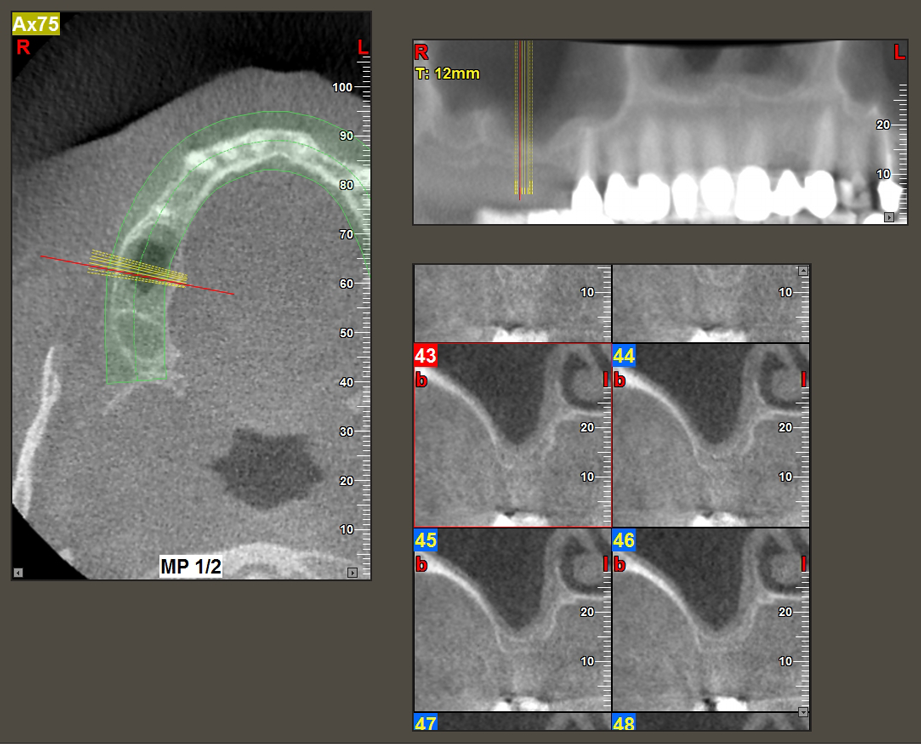

Une patiente de 49 ans, non fumeuse et sans antécédents médicaux remarquables, a été orientée vers notre cabinet de chirurgie orale pour l’extraction chirurgicale de la dent 16 préalable à la pose d’un implant. Après l’extraction, la patiente a rencontré de légers problèmes de sinusite, à la suite de quoi nous avons commencé par attendre six mois avant de prendre la mesure. À l’endroit prévu pour la pose de l’implant, l’os résiduel mesurait 3-4 mm de haut (Fig. 1 et 2).